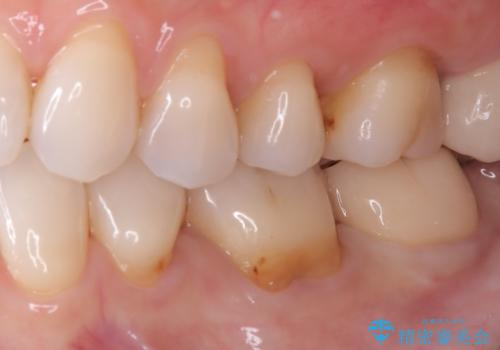

- 主訴:歯に穴が空いていて沁みる

左下7番目の歯の頬側に大きな穴(う蝕によるもの)が空いており、う蝕の範囲が大きく神経を及ぼしている可能性も説明し生活歯髄療法とクラウンでの補綴治療を行うこととなりました。

治療に入る前に歯髄診断を行った結果、正常反応を示しました。

左下7頬側歯頚部に大きくできたう窩内のう蝕を除去していき、生活歯髄療法(間接覆髄法)を行いました。